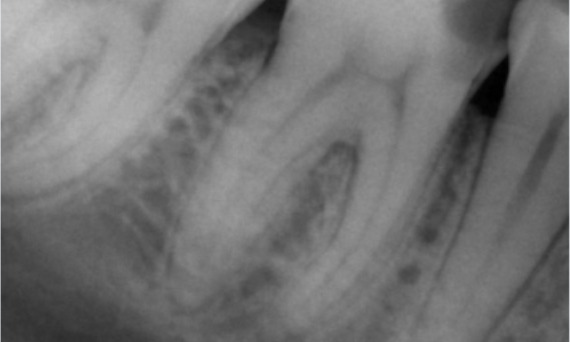

Antes: Durante la evaluación, se detectó una lesión de caries relacionada con el primer molar inferior derecho. El examen radiográfico reveló la proximidad de la lesión al cuerno pulpar, y al combinarla con la queja principal, se concluyó un diagnóstico final de pulpitis irreversible crónica.

Después: La cavidad de acceso se realizó de la forma más conservadora posible. TruNatomy fue el sistema de elección debido a la juventud del paciente. Necesitábamos conservar la mayor cantidad de dentina para aumentar la capacidad dental de superar la carga oclusal y aumentar la longevidad de la restauración final.

El Cairo, Egipto